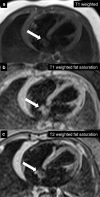

The Society for Cardiovascular Magnetic Resonance (SCMR) is an international society focused on the research, education, and clinical application of cardiovascular magnetic resonance (CMR). The SCMR web site ( https://www.scmr.org ) hosts a case series designed to present case reports demonstrating the unique attributes of CMR in the diagnosis or management of cardiovascular disease. Each clinical presentation is followed by a brief discussion of the disease and unique role of CMR in disease diagnosis or management guidance. By nature, some of these are somewhat esoteric, but all are instructive. In this publication, we provide a digital archive of the 2019 Case of the Week series as a means of further enhancing the education of those interested in CMR and as a means of more readily identifying these cases using a PubMed or similar search engine.

Keywords: Cardiac tumor; Cardiomyopathy; Eosinophilic granulomatosis; MRI.